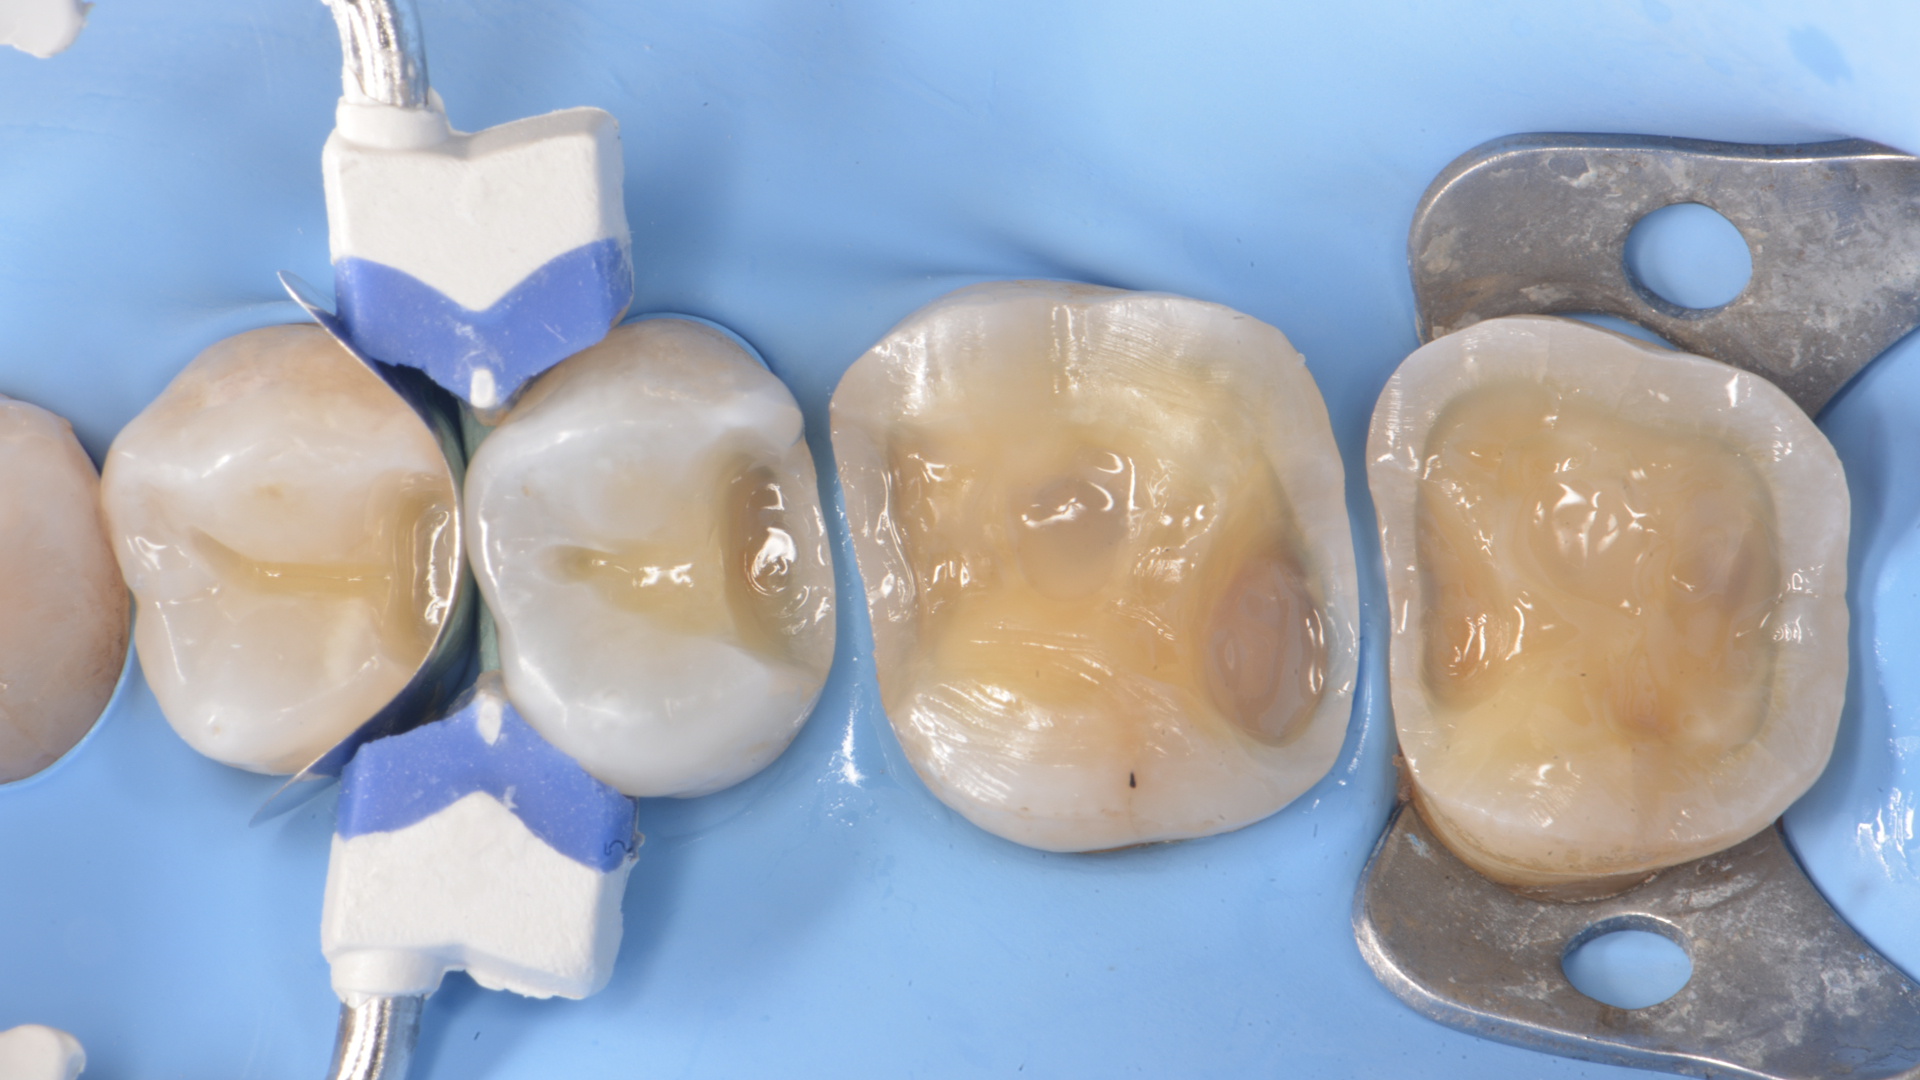

Figure 6

Figure 5. Restoration of distal wall 1.5 (Garrison Composi-tight 3D Fusion System)Figure 6.  Restoration 1.4-1.5 completed. Final Preparations 1.6 -1.7